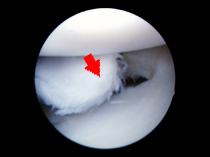

- この症例はプロサーファー、膝外側半月板損傷で関節鏡視下手術を行いました。

- 1.

- 半月板中央で断裂しています。

- 2.

- 専用のパンチを用いて損傷部を切除します。